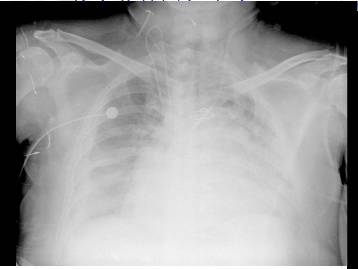

2.超滤前后胸片变化

超滤前

超滤后2日